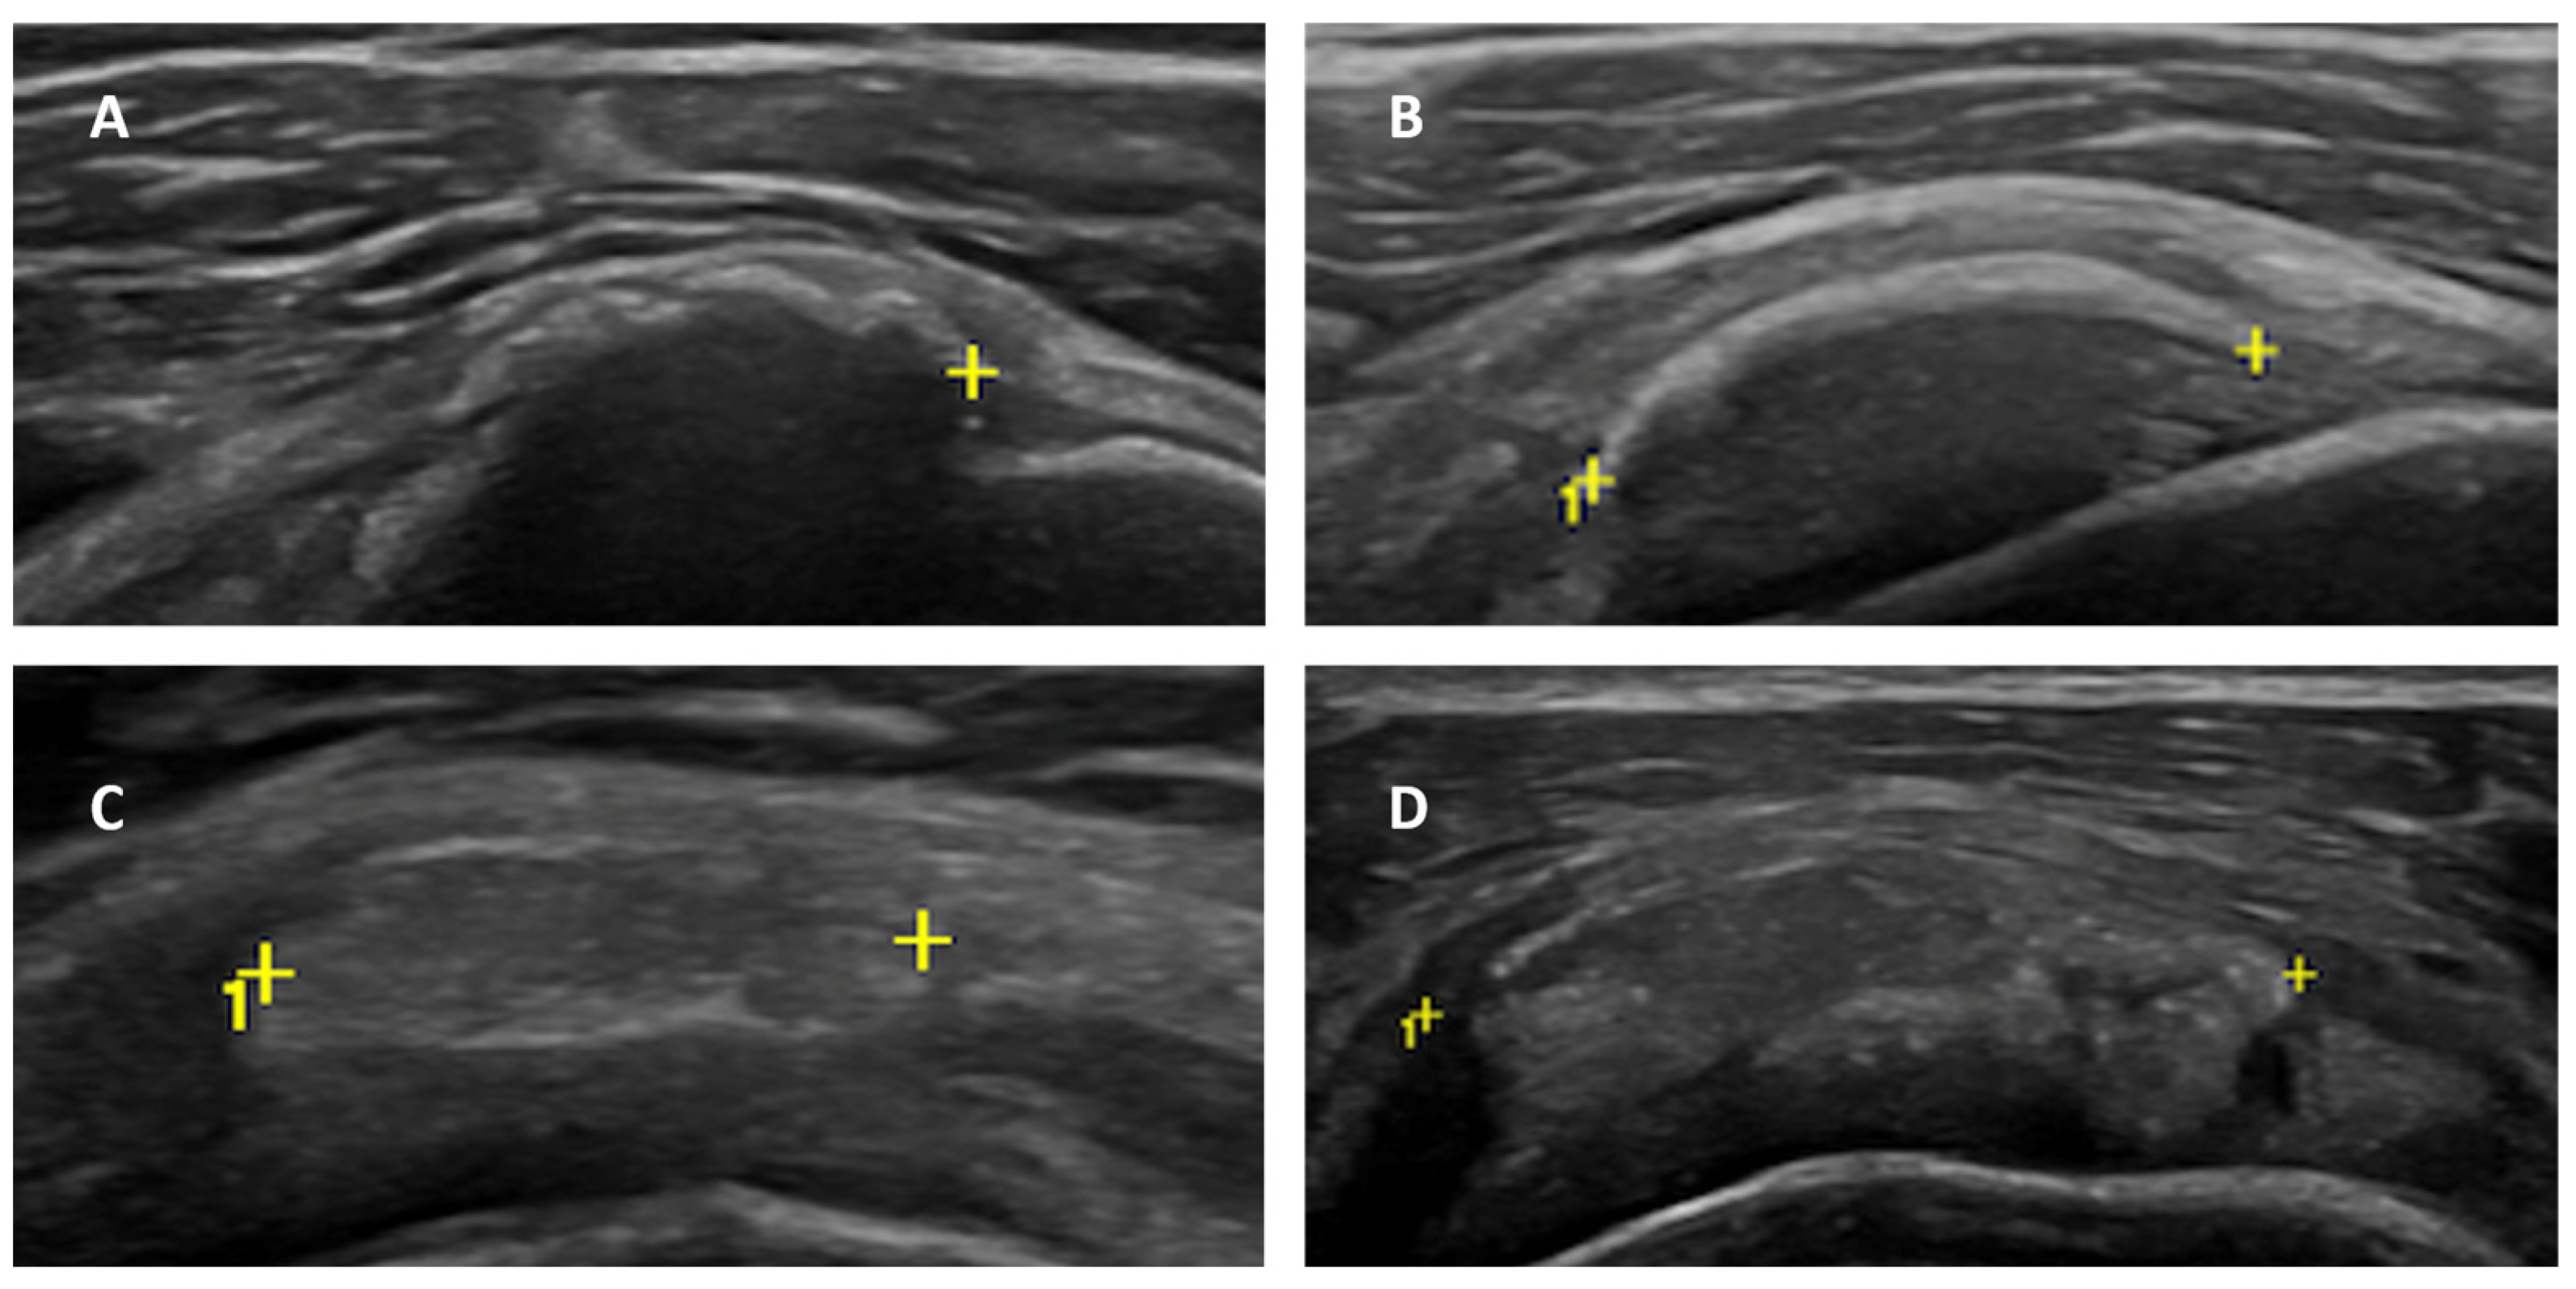

- Calcific deposit maturation stage, according to the classification proposed by Chiou et al. [21]: stage I (arc-shaped with complete posterior acoustic shadowing), stage II (fragmented or punctate with partial posterior acoustic shadowing), stage III (nodular, without posterior shadowing) and stage IV (echogenic with cystic degenerative areas and without posterior shadowing);

3.2. Calcific Deposit Maturation Stage

3.3. Axillary Pouch (AP) Thickness

3.4. Rotator Interval (RI) Thickness and Effusion within the LHBT Sheath